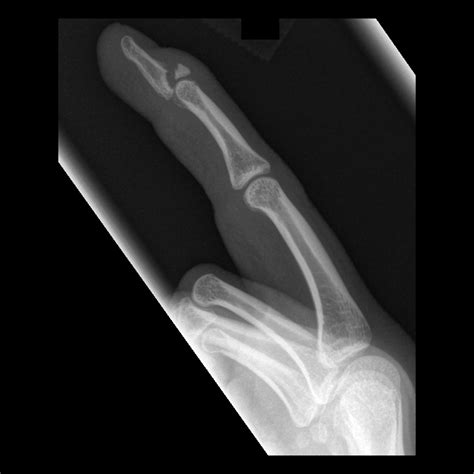

• Deformity or misalignment of the finger.

Diagnosing a Broken Index Finger

Diagnosing a broken index finger typically involves a physical examination and imaging tests. Your healthcare provider will:

• Examine the injured finger to assess the extent of the damage.

• Order X-rays to visualize the bone and determine the type and severity of the fracture.

• In some cases, additional imaging tests such as CT scans or MRIs may be required for a more detailed view.

Based on the findings, your healthcare provider will recommend the appropriate treatment plan.